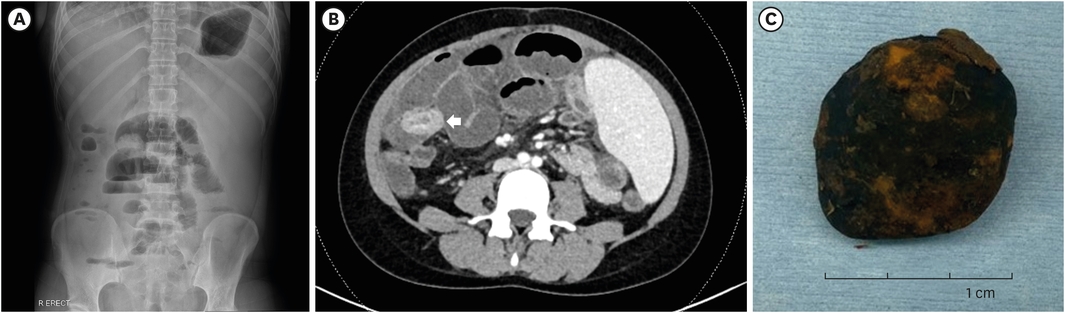

She was admitted to the pediatric department for conservative management of cholangitis and ileus. Liver ultrasonography was done on the 2nd day of admission. It revealed acute on chronic cholangiohepatitis. Echogenic material with posterior shadowing at portoenterostomy site was found in liver ultrasonography at two months prior to the ED visit. This finding was substituted by echogenic fluid at the same site (Fig. 1A). Abdominal computed tomography (CT) taken around the same time revealed stone-like material at the same location (Fig. 1B). Intravenous teicoplanin and meropenem were applied. They were also used in the previous event. However, on hospital day 9, she started to complain more severe abdominal pain. Gaseous distension in the X-ray did not improve. It seemed to be exacerbating (Fig. 2A). Abdominal CT was taken on hospital day 12. It showed long segmental dilatation of the small bowel with obstruction with a dense material that was about 3.1×3.9 cm size in the ileum. Distally migrated biliary stone was suspected for the dense material (Fig. 2B).

Fig. 1

Stone-like material in the portoenterostomy site (A) in liver ultrasonography and (B) in computed tomogram found at 2 months before visiting emergency room (arrow).